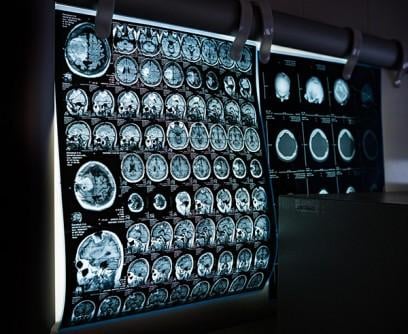

A strategic collaboration will focus on bringing advanced digital innovation and the newest generation of imaging technologies to UC San Diego Health to deliver high-quality, timely and consistent care that meets the individual patient’s health care needs. (Photo: Pixabay/UC San Diego Health)

Through the joint effort, UC San Diego Health will leverage the newest generation of imaging systems, including X-ray, ultrasound, computed tomography (CT), positron emission tomography (PET), magnetic resonance imaging (MRI), in combination with artificial intelligence (AI) tools to help optimize efficient processes.